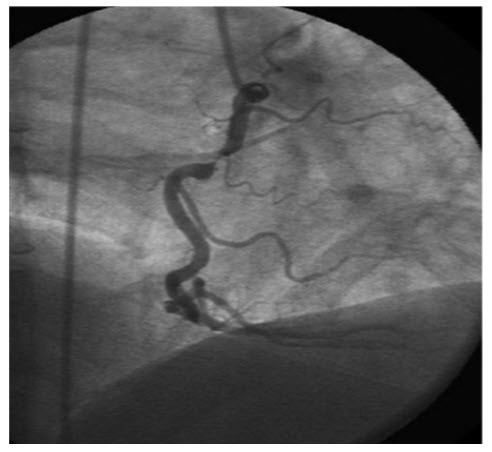

A 67-year-old man known for hypertension and hypercholesterolemia presented significant ST elevation in inferoposterior leads during the treadmill test. The angiogram shows (Fig. below)

A. Severe LCX stenosis

B. Severe left main trunk stenosis

C. Severe LAD stenosis

D. Severe RCA stenosis

E. No significant coronary artery stenosis